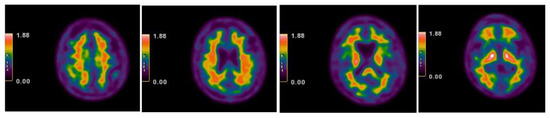

| 2013 | FDG-PET | Hypometabolism in the right and left premotor cortex |

| 2015 | Neurological assessment FDG-PET | Mild isolated motor speech disorder hypometabolism; more extensive involving left temporal gyrus, frontal gyrus bilaterally, cingulate, caudate, and thalamus bilaterally |